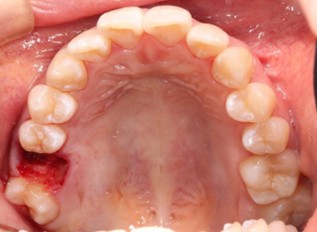

20代 男性

治療前

治療後

治療後- リスク・副作用

(薬・注射・レントゲン・CT・データ分析・骨造成・サージカルステント・血液検査・仮歯) - 年齢/性別

- 20代/男性

- 患者の具体的な症状

- 1年前に左上12 右上1の根の治療をし、その後放置していたら、左上2が破折した。

左上2インプラント補綴 左上1右上1オールセラミック装着。

歯根破折と虫歯による痛み、審美障害を主訴として来院。 - 検査方法

- コーンビームCT、レントゲン撮影

- 診断結果

- 左上2 歯根破折

- 治療詳細

- 左上抜歯後、インプラント埋入1本

骨造成あり 局所麻酔

インプラント治療後、左上1右上1セラミック修復2本 - 通院回数

- 9回

- 治療期間

- 12か月